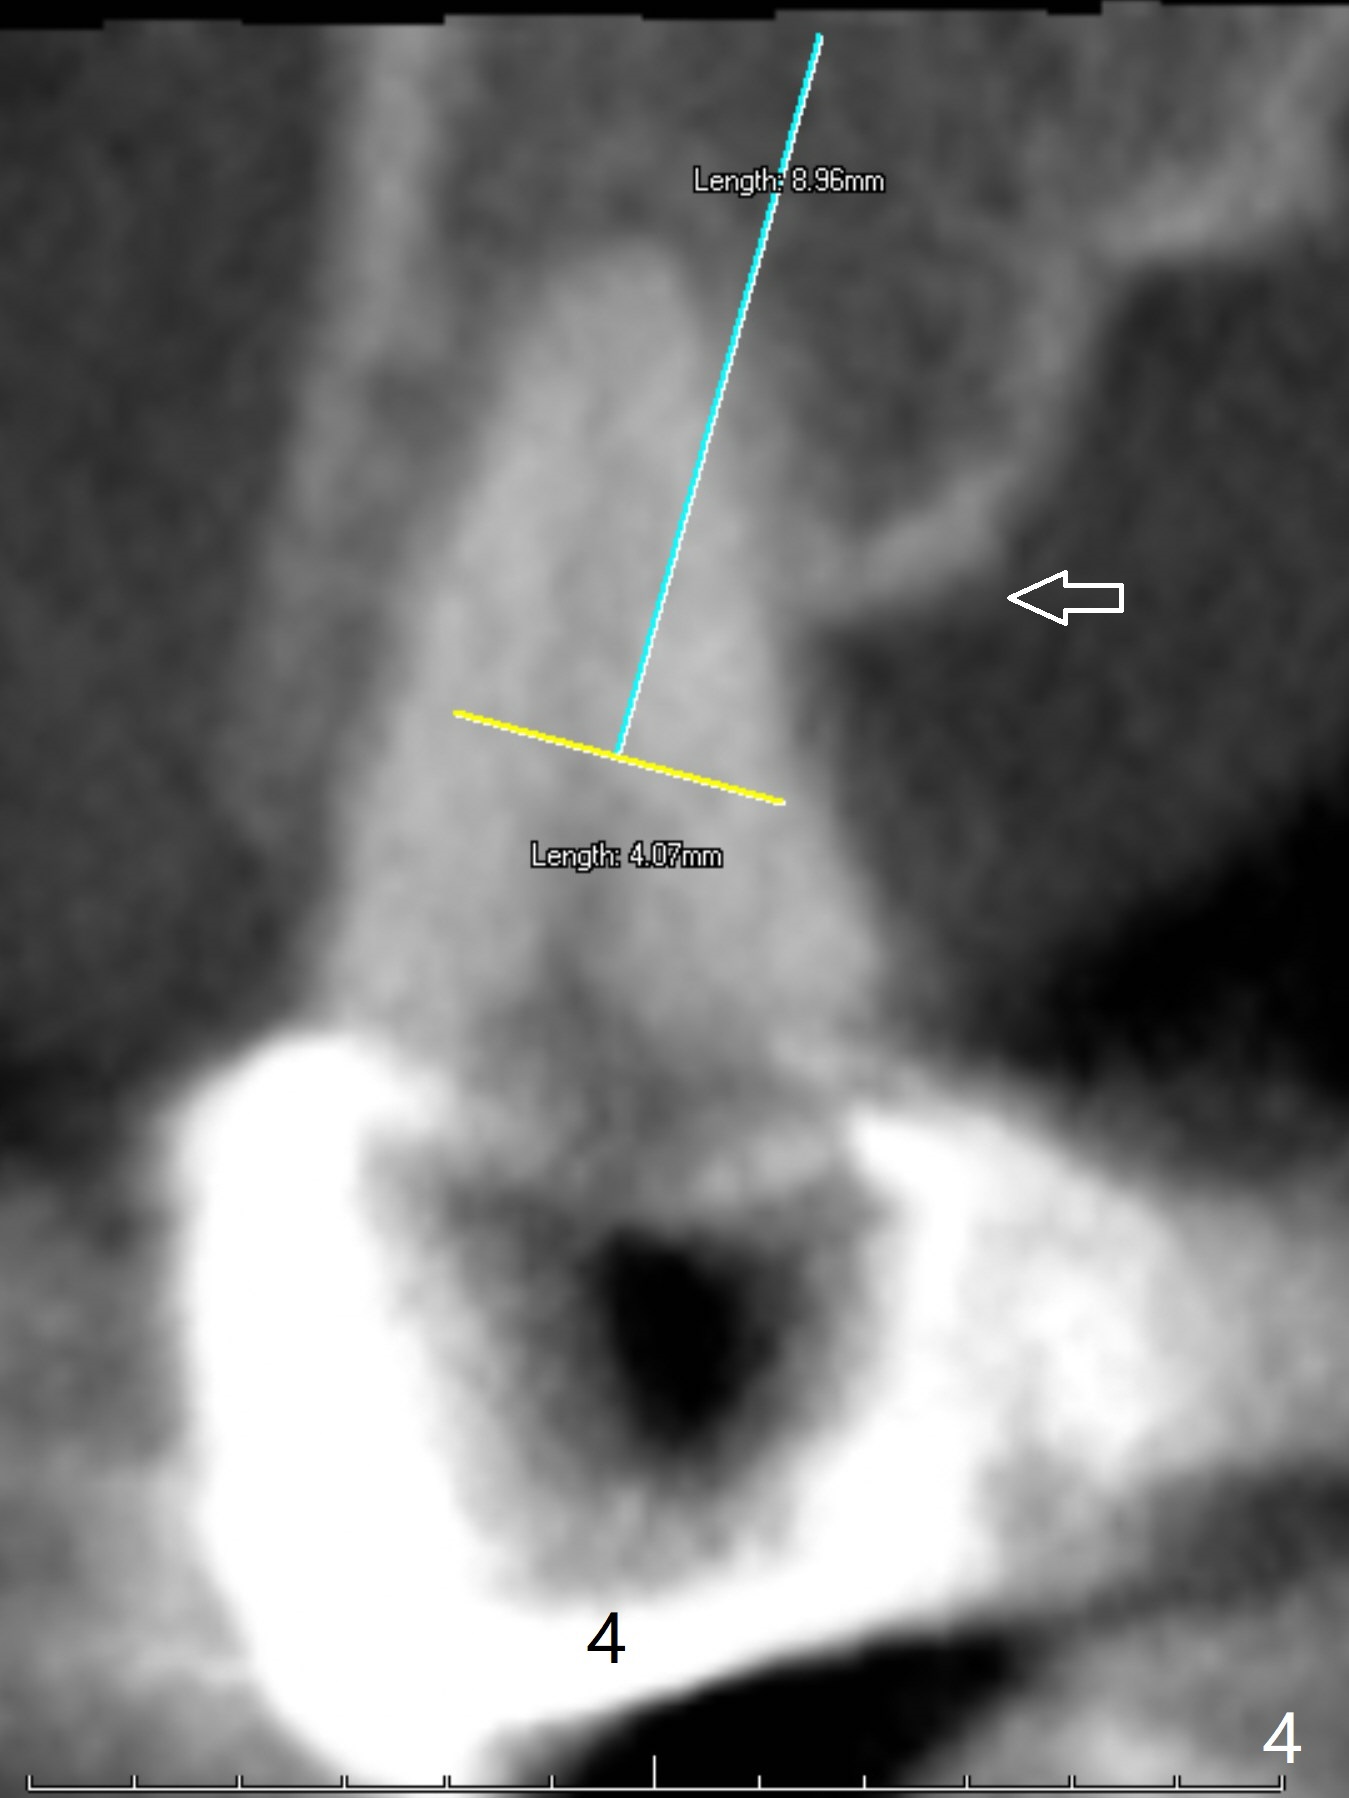

A 43-year-old woman has a failing upper right bridge (Fig.1: #2-5). While the abutment at #5 has apparently palatal open margin (Fig.2,3) and that at #4 has severe palatal bone loss (Fig.4 arrow), that at #2 has the poorest prognosis (Fig.6,7). Panoramic X-ray or PAs will be taken because of CBCT cone cut when the patient returns for #30 and 31 post-implant follow-up. Alginate impression will be taken for the upper right quadrant for provisional. The bridge will be sectioned between #3 and 5 (Fig.1 red lines) to determine salvageability of the abutments at # 4 and 5. If the latter are ok, the abutment at #2 will be extracted (expected to be loose) and implants will be placed at #2 and 3. If #4 is bad while #5 is ok, the former will be extracted and implants will be placed at #2 and 4 with a bridge. If #5 is bad while #4 is ok, implants will be placed at #2, 3 and 5.